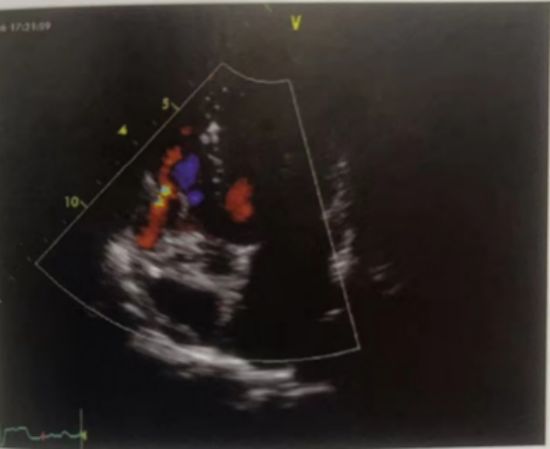

二、冠状动脉—右室瘘

超声切面:心尖五腔心(非标准切面)

超声可见:瘘管开口于右心室,瘘口位于右心室瓣环处,三尖瓣前瓣的根部,也可位于右室心尖部,瘘口处双期左向右分流,可导致右心容量负荷增加,右心扩大(图7)

图7 心尖五腔心彩色多普勒显示左冠状动脉瘘入右心室